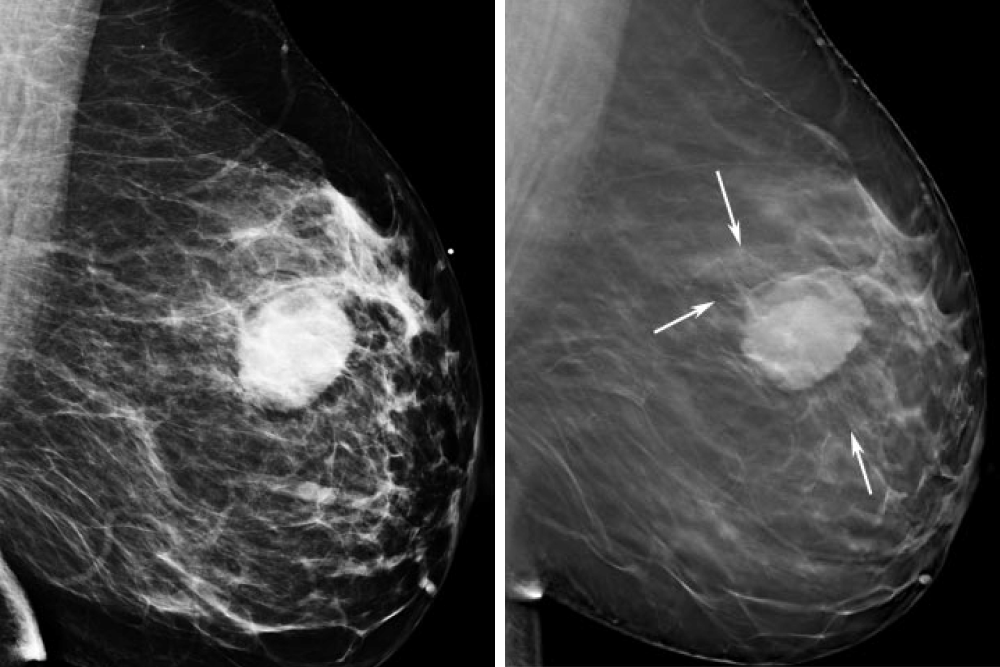

Феномен гипердиагностики в маммографии: примеры и иллюстрации

Раздел: Образы вокруг